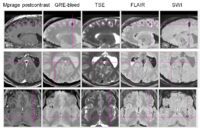

Over the past 4 months, the UCLA team has developed a sophisticated protocol for image segmentation and model generation, which has been applied to three representative TBI patients with spectacular results. This standard protocol has been confirmed to be optimal for TBI case analysis in 3D Slicer. Specifically, brain lesions adjacent to CSF were segmented from volumes acquired using FLAIR, GRE imaging, TSE T2-weighted volumes as well as DWI. Because SWI is generally superior to GRE and T2-weighted imaging to detect hemorrhagic lesions, volumes acquired using the former modality were used to identify micro-hemorrhages. Images that were additionally available in the context of our protocol were used to confirm segmentation accuracy as well as to illustrate the additional capabilities of 3D Slicer to segment images from a variety of MR data sets and combination of sequences. Throughout the past several months, the UCLA team has demonstrated the usefulness of semi-automatic segmentation tools available in 3D Slicer software, including the Atlas Based Classification (ABC) segmenter. As opposed to other specialized segmenters where access is often restricted from outside users, the ABC segmenter is freely available as a segmentation module in 3D Slicer. The method is automatic, its execution requires minimal user supervision, and its appropriateness for TBI case analysis is excellent. In addition, the ABC segmenter possesses the ability to perform co-registration of an arbitrary number of MR volumes acquired using various sequences. This makes ABC highly suitable to the UCLA multimodal TBI imaging paradigm, where as many as 12 distinct sequence types are employed in the context of a sophisticated TBI analysis protocol. At UCLA, tissue-type segmentation has already been used to calculate the total volumes of selected structure types (ventricular system, non-hemorrhagic lesions, and hemorrhagic lesions, white matter and gray matter). Volume changes have been computed as the ratio of the difference in volume between the follow-up and acute baseline time points, to the volume at the latter time point. In addition to these measures, the UCLA team has also computed five measures of atrophy, namely the bifrontal index, the bicaudate index, Evan’s index, the ventricular index and Huckman’s index. These measures as computed in Slicer have been found to be in excellent agreement with previous results available in the TBI literature.